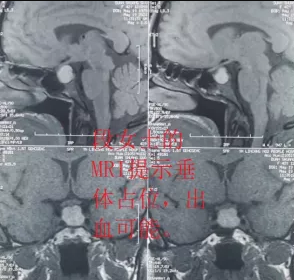

完善檢查后,段女士被確診為無功能性垂體腺瘤并卒中。通過積極術前準備,楊金雷主任帶領的外一科醫護團隊,在省級專家指導及我院麻醉手術室的精誠協作下,為段女士開展了顯微鏡下經鼻蝶垂體腺瘤切除術。手術歷時1.5小時后順利結束。